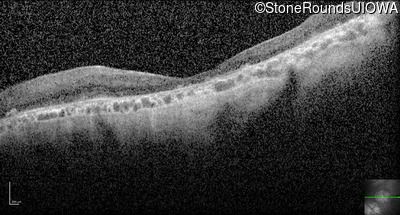

Optical Coherence Tomography - Left - Hand Motion 6" sc

Exemplar / OCT Stack